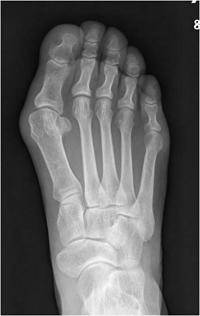

소건막류는 새끼발가락이 엄지발가락 쪽을 향해 휘는 것으로, 새끼발가락 뿌리 관절 부분이 바깥쪽으로 튀어나오는 질환이다. 소건막류는 주로 발볼이 넓은 사람에게 나타나며 무지외반증(엄지발가락이 검지 발가락 쪽으로 휘는 질환)과 동반되는 경우가 많다. 소건막류가 있는 사람이 신발을 신고 걸을 때 새끼발가락 옆 돌출된 뼈 부위가 빨갛게 변하면서 굳은살이 생기거나 새끼발가락이 아픈 증상을 보인다. 또한, 발가락 통증 때문에 무게 중심이 흐트러져 무릎·골반·허리·어깨·관절 등에 부담이 간다.

소건막류는 자신의 발볼보다 작은 신발을 오랫동안 신었을 때 발병한다. 발볼에 맞지 않는 신발을 신으면 새끼발가락 관절에 마찰과 압박이 생겨 뼈가 바깥으로 휘는 변형으로 이어진다. 우리나라와 같이 좌식생활을 하는 문화권에서는 바닥과 새끼발가락의 마찰이 잦기 때문에 소건막류가 쉽게 생길 수 있다. 소건막류를 치료하지 않고 내버려 두면 뼈의 휘는 정도가 심해지고, 신발을 신을 때 새끼발가락 주변에 물집이 생길 수 있어 주의가 필요하다.